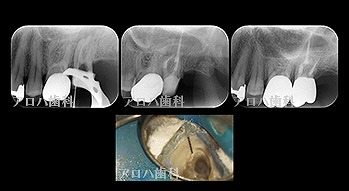

case5

左:頬側よりGP挿入。MB根尖の透過像と一致。

P根にも透過像。穿孔を疑う。

右:術後1年。

左:術前

右:術後1年

P根の穿孔封鎖

頬側の瘻孔